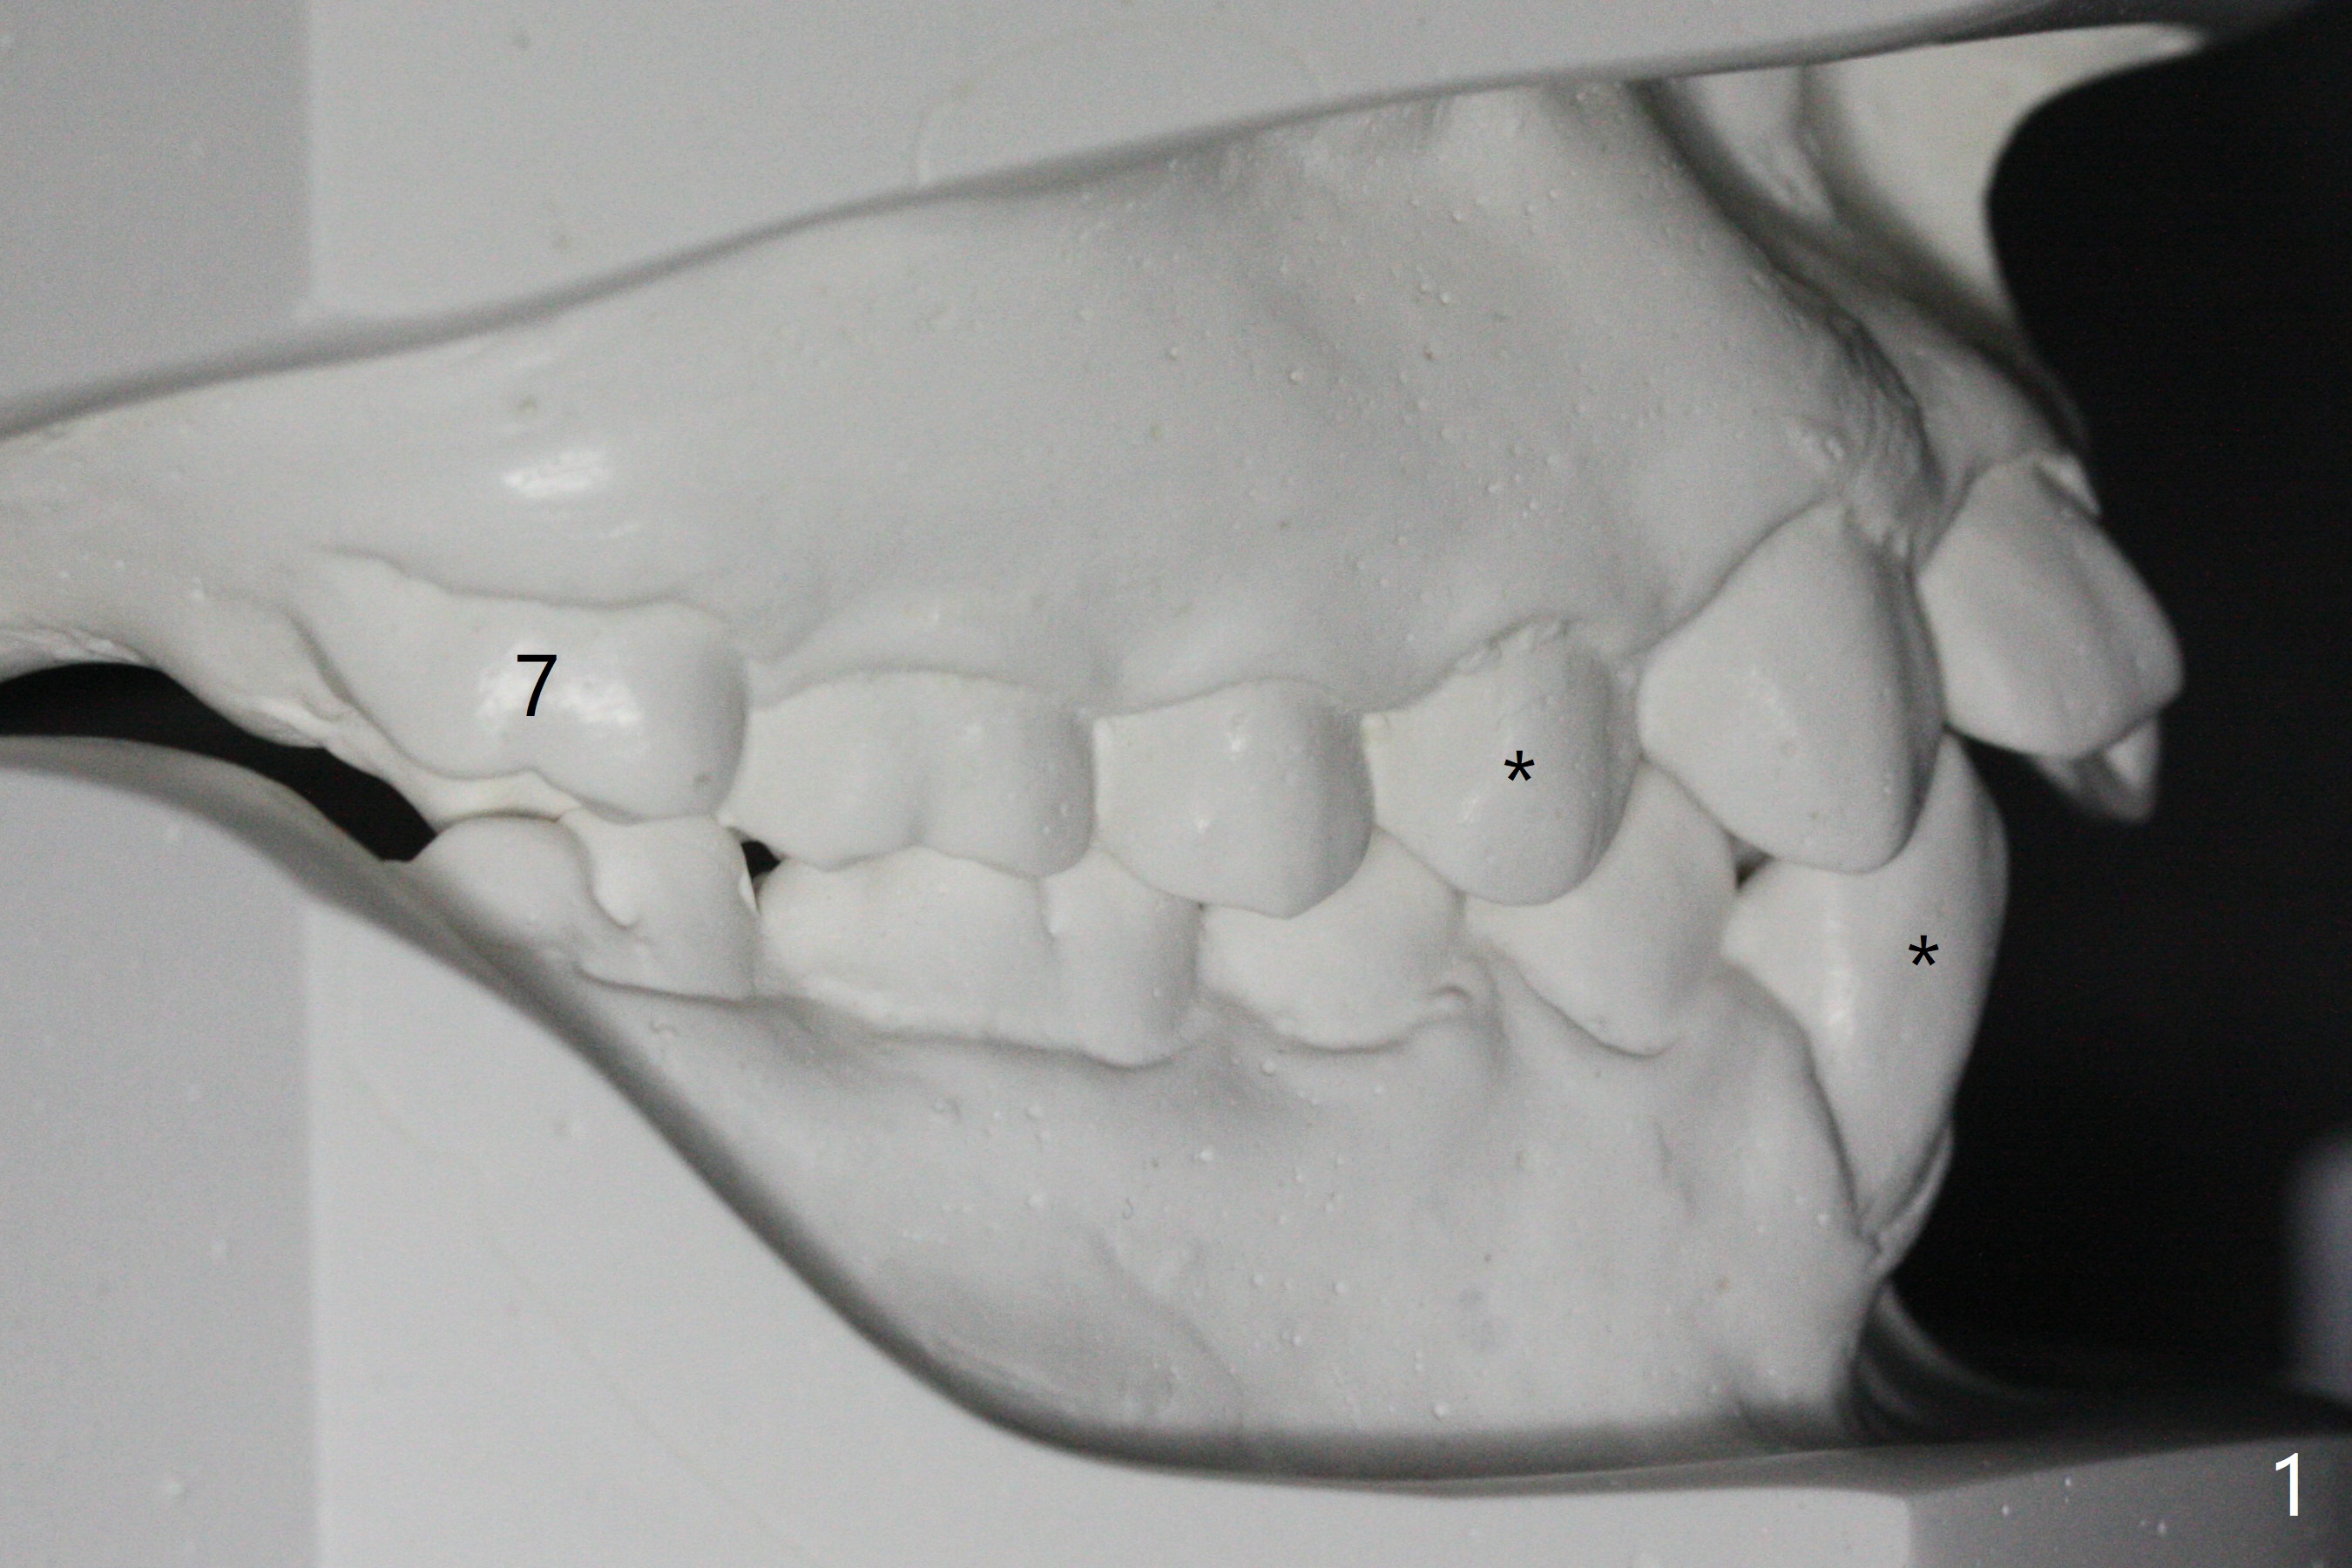

Brackets and Bands will be placed 2 months post extraction (Fig.1-3: *). UR7 (overjet; Fig.1 (7), 2 (arrow)) will be retracted early using LR6 and 7 as anchorages. Because of good posterior interdigitation (Fig.1), U3s and LL3 will be distalized using closed coil spring between 3 and 6 (7 preferrable retrospectively). When this is finished, retract 4 incisors (each arch) together using a posted wire and the same closed spring.